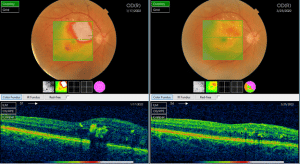

4. OCT macular (tomografie în coerență optică) : evaluează prezența, extensia si evoluția edemului macular după tratament.

Foto 4. Reducerea edemului macular după tratament injectabil cu anti-VEGF